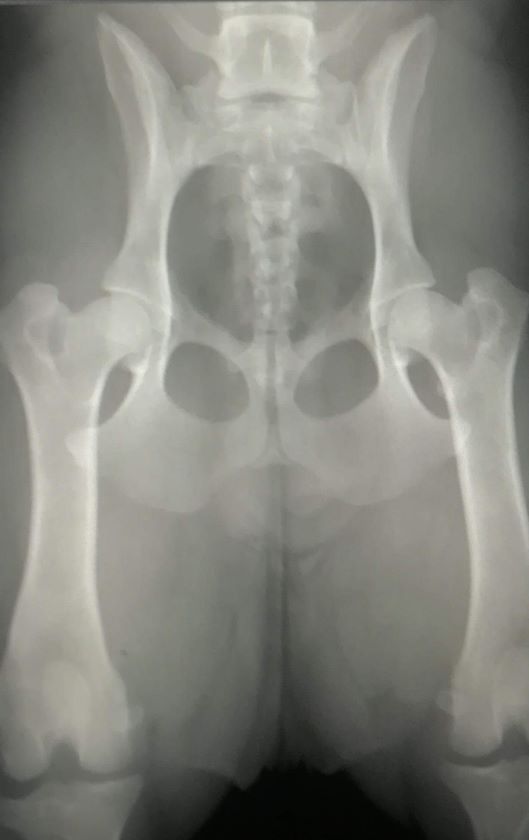

Nonette de Jommokk

femelle

Spitz des Visigoths

née le

23/04/2017